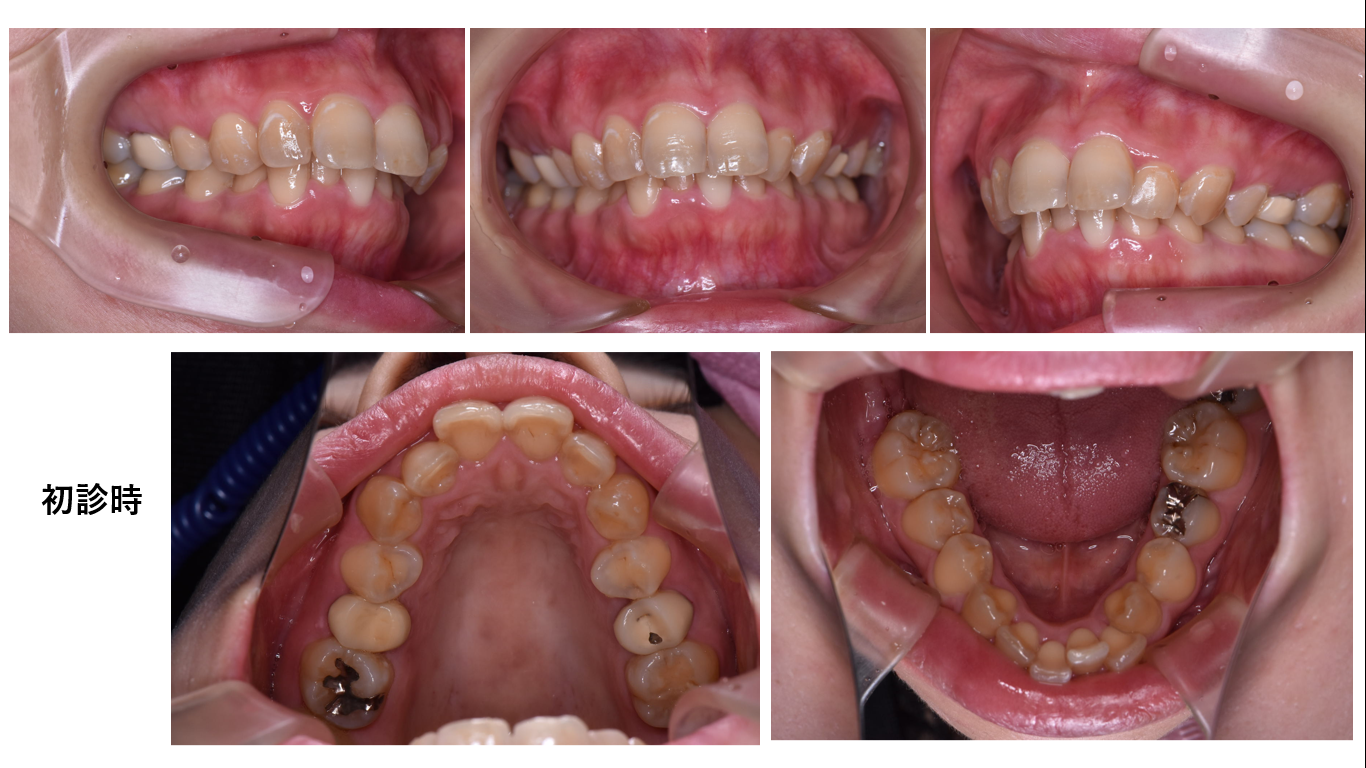

矯正症例145 叢生を伴うAngleⅡ級1類上顎前突

初診時34歳女性、治療期間4年2か月、抜歯部位:上顎左右5番、下顎左右5番、治療費総額112万円(税込み)

下顎歯列弓が重篤なv字歯列弓です。これを修正するのに通常の矯正より時間がかかります。更に初診時34歳の年齢であることから時間が大幅にかかります。

右上7番は歯肉縁下カリエスで抜歯となりました。動きが遅い症例でしたが、コルチコトミーを併用しても良かったと思っています。